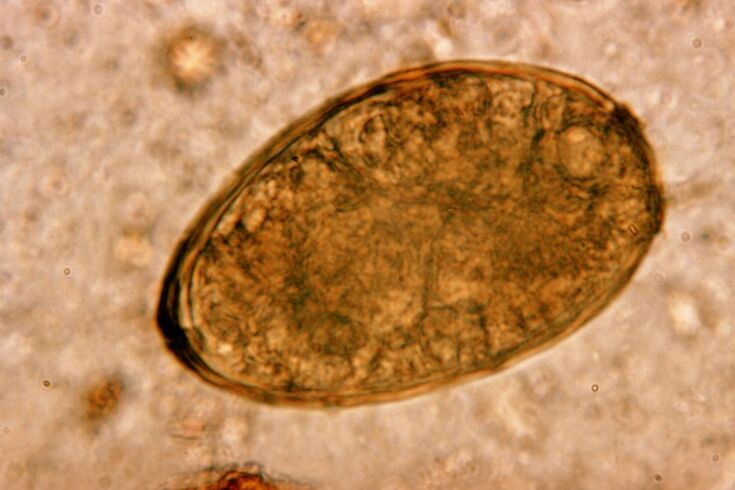

The fluke lives in the lungs in pairs, creating cysts in the bronchi.Infestation occurs when crabs and crabs infected with the parasite are eaten.Once in the gastrointestinal tract, the fluke penetrates the peritoneum and reaches the lungs through the diaphragm, causing a persistent cough in the patient.

The small helminth lung fluke, which belongs to the trematode class, is "specialized" for parasitizing especially in the lungs.It causes much more serious problems in the respiratory system than, for example, roundworms.

At the site of its localization, infiltrates and bleeding occur, resulting in cavities filled with decomposing worm metabolites, dead parasites and lung tissue.The damage from the lung fluke is further compounded by the fact that it is a long-lived liver and can live in the host's body for up to 20 years.